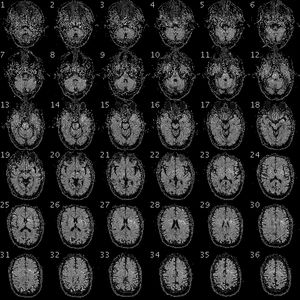

기능자기공명영상법(fMRI) 스캔을 통해 얻은 데이터는 분석 전에 여러 단계의 전처리 과정을 거친다. 스캐너는 각 TR(반복 시간)마다 피험자의 머리에 대한 3차원 볼륨 이미지를 생성하며, 이는 각 복셀의 강도 값 배열로 구성된다. 여러 시간대에 걸쳐 촬영된 이 볼륨들을 결합하여 4차원 볼륨 데이터를 만들고, 이것이 분석의 시작점이 된다. 전처리 과정은 데이터의 노이즈를 줄이고 분석의 정확도를 높이는 것을 목표로 한다.전처리의 첫 번째 단계는 일반적으로 슬라이스 타이밍 보정(slice timing correction)이다. MR 스캐너는 뇌의 각 슬라이스를 약간 다른 시간에 촬영하기 때문에, 각 슬라이스는 서로 다른 시점의 뇌 활동을 나타낸다. 슬라이스 타이밍 보정은 모든 슬라이스의 시간 기준을 동일하게 맞춰주는 과정이다. 이는 각 복셀의 시간 경과 데이터가 부드러운 곡선을 그린다고 가정하고, 샘플링되지 않은 시점의 값을 보간하여 계산한다.